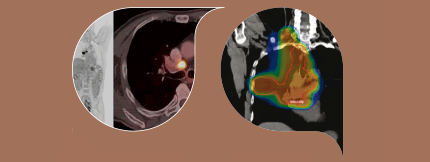

基本原理-染色图

索拉契图摩斯

2019更新二后端版面Thracic图理学基础知识包括新章节Immuno肿瘤和Oncogene定型肿瘤定向治疗今天下载拷贝